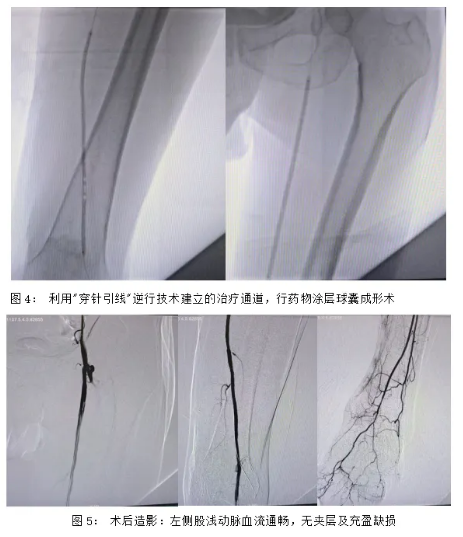

面对传统顺行开通失败的高难度病例,手术团队创新采用:

1.逆穿技术

在超声引导下精准穿刺腘动脉P2段,突破顺行开通的解剖限制

2."穿针引线"汇合

0.018英寸导丝与翻山鞘管双向对接,成功建立治疗通道

3.药物涂层球囊成形

应用紫杉醇涂层球囊抑制内膜增生,显著降低再狭窄率(较普通球囊降低50%)

术后造影显示:

•术前闭塞的股浅动脉恢复通畅,股深动脉分支血运改善;